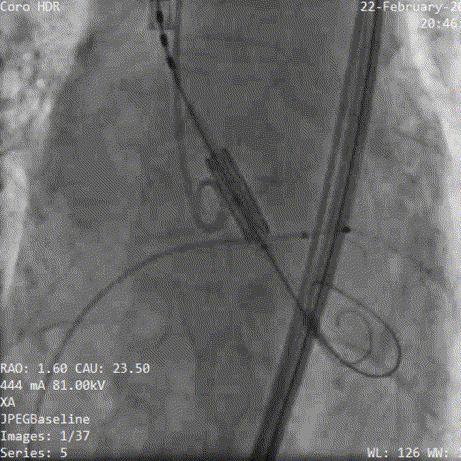

术中影像:

3.精细调节位置,改变投照角度,获取瓣架切线位定位

4.展开瓣膜